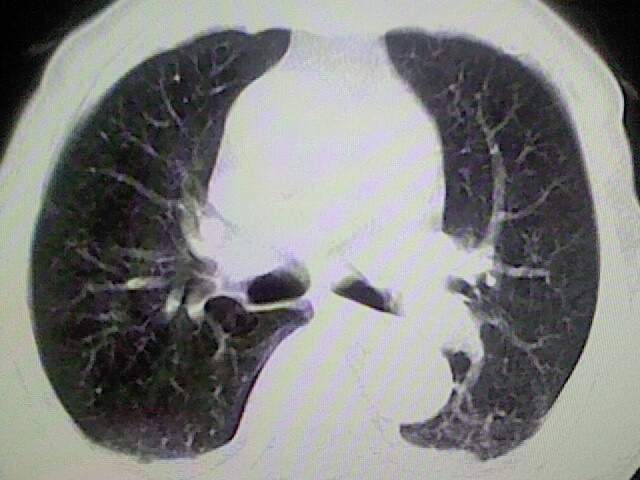

以下是引用zsl6918在2008-8-28 16:49:00的发言:[br]双肺炎性病灶,食管狭窄估计与心房增大压迫所致。

以下是引用xulianj在2008-8-28 20:36:00的发言:[br]慢支肺气肿伴感染,右上肺陈旧性结核;食道建议胃镜检查。

以下是引用wqs571018在2008-8-28 21:18:00的发言:[br]慢支继发感染,右上肺陈旧性结核;食道建议胃镜检查。